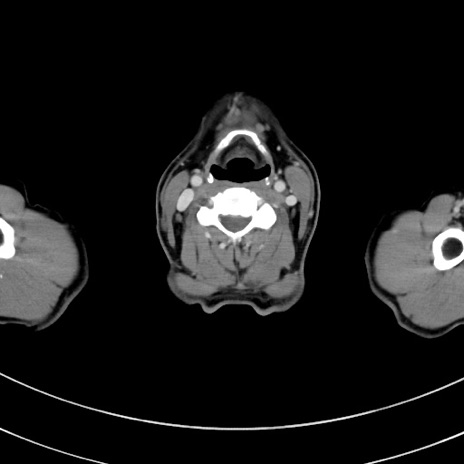

冠状断像